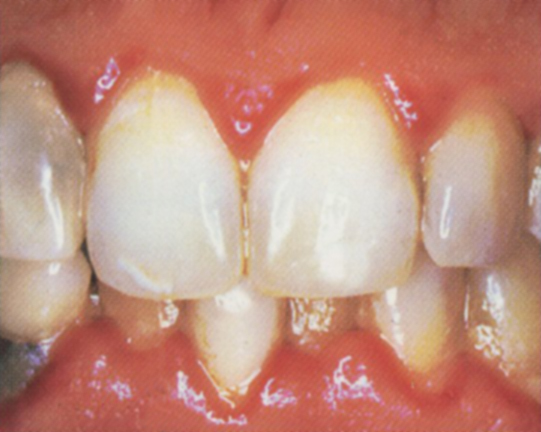

Střední parodontitis obr. 4

- dásně ustupují, odhalují se citlivé zubní krčky

- zuby vypadají delší

- zarudnutí, otok a krvácení dásní je výraznější

- dásně jsou citlivé až bolestivé

- zápach z úst, poruchy chuti

- sondovatelná hloubka dásňového žlábku se prohlubuje na 4-6 mm

- na rtg je patrný úbytek horizontální i vertikální úbytek kosti